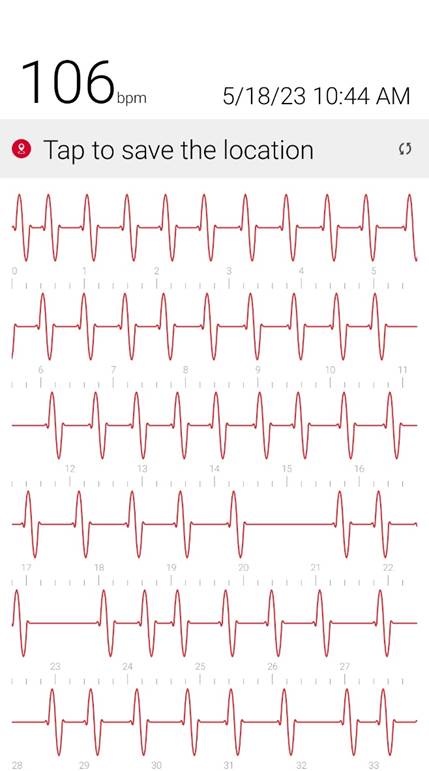

Initial ID consult diagnosed local tetanus based on clinical symptoms and recommended oral Metronidazole 500mg every 6 hours as an outpatient. Autonomic involvement developed with tachycardia and cardiac arrhythmia, along with episodes of sudden sweating. Loud noises made twitching/spasms worsen. Intermittent twitching continued to be present bilaterally in the body, face, jaw & tongue. Symptoms were suppressible with benzodiazepine. Tetanus IM IG 500 IU was recommended and obtained. After initial 2 week course of metronidazole was discontinued symptoms worsened again when patient would walk. Multiple trials of oral Metronidazole 500mg every 6 hours were attempted with some improvement while on the antibiotic but then return and worsening of symptoms again once antibiotic was discontinued.

incrementally, then once twitching had reached the spinal level, muscle twitching spread to the bilateral muscles of the body with cardiac arrhythmia & autonomic involvement/ sweating. A trial of antibiotic Keflex (cephalexin ) was suggested, which only at high dose (1000mg PO every 6 hours), helped keep spasms localized to the left foot mostly but symptoms would worsen and generalize if antibiotic Keflex (cephalexin) was stopped for more than 2 days. Benzodiazepine was increased to every q6 hours to reduce muscle twitching that had become constant in the left foot. Symptoms improve when patient does not walk or avoids any pressure or bending of left big toe and symptoms worsen when patient walks or stops antibiotic and has been unable to stop antibiotic for the past year and a half without worsening of symptoms. When antibiotic is stopped for 2 days bilateral jaws begin to snap shut intermittently involuntarily and cardiac arrhythmia/ heart block reoccurs. Symptoms worsen further after 4 days off antibiotic. Local

Oral Keflex (cephalexin) 1000mg 4 times a day & IM Bicillin LA 2.4 million units 3 times a week were restarted with improvement in bilateral body muscle twitching but twitching / spasms locally in the left toes and foot continued. This regimen was continued for 7 weeks. One day after discontinuing oral Keflex (cephalexin) (and 3 days after the last bicillin IM shot) spasms again began at the left big toe, left toes and left foot, progressed up the left leg to the left gluteal muscles and again once the spinal level was reached spasms spread to the right side of the body and then upper body and by 1 and 1/2 days after all antibiotic was discontinued, arrhythmia/heart block began again. Oral Keflex 1000mg 4 times a day was restarted (cephalexin). Benzodiazepines had been continued throughout.

3) Cardiac Arrhythmia / Heart Block occurs during generalizations

When antibiotic is discontinued or with increased walking, rhythm returns to normal when antibiotic is restarted after a few days.